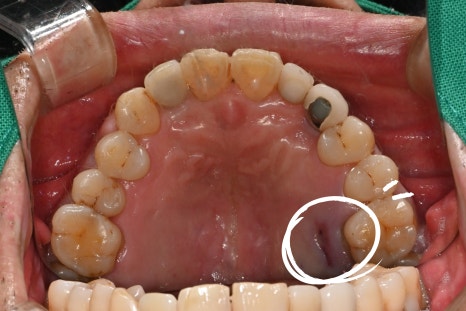

초진 내원당시

이번 케이스는 68세 남성 환자로, 잇몸이 심하게

붓고 통증이 발생한 상태에서 내원하셨습니다.

기존에 약을 복용하셨지만 증상이 호전되지 않았고,

어금니 부위의 통증이 점점 심해지는 상태였습니다.

검사 결과 어금니 주변 잇몸 내부에 고름이 형성된

치주농양 상태였으며, 뿌리 주변 뼈가 손상된 상태가

확인되었습니다.